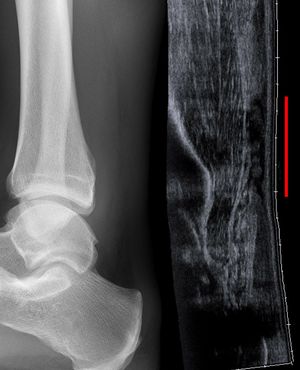

![]() صورة خلفية للقدم والساق، توضح وتر أخيل. | |

![]() صورة خلافية للكاحل البشري، ويشمل وتر أخيل. | |

التصوير الشعاعي يمكن أن يستخدم أيضاً لتعرف انقطاعات وتمزقات الوتر العقبي بشكل غير مباشر. التصوير الشعاعي يستخدم الأشعة السينية لتحليل نقطة الإصابة. لا تكون هذه الوسيلة فعالة جداً في تحديد إصابات النسيج الرخو. تنشأ الأشعة السينية عندما تصطدم الإلكترونات عالية الطاقية بمصدر معدني. يتم الحصول على صور الأشعة السينية من خلال استخدام خصائص التوهين المختلفة للأنسجة ذات الكثافة (مثال: الكالسيوم في العظم) و أنسجة أقل كثافة (مثال: العضلات) عندما تمر هذه الأشعة من خلال النسيج و تلتقط على فيلم. يتم اللجوء للأشعة السينية عامة لتحسين تصور الأجسام ذات الكثافة مثل العظم، و أما النسيج الرخو فيبقى نسبياً غير متمايز في الخلفية. التصوير الشعاعي لديه دور ضئيل في تقييم إصابة الوتر العقبي و ذو فائدة أكثر لاستبعاد الإصابات الأخرى مثل الكسور العقبية.[5]